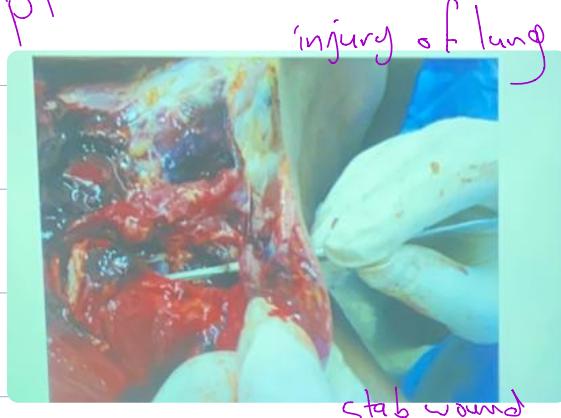

- Description: Cut/Stab to neck. Injury of lung.

- Note: Stab wound has more depth than cut wound.

- Type: Stab penetrating wound to heart.

- Organ: Heart.

- Cause of death: Hemorrhage.

- Characteristics: A.M Wound.

Station 16: Stab Wound

- Findings: Stab to apical lung, difference between stab and incised wound